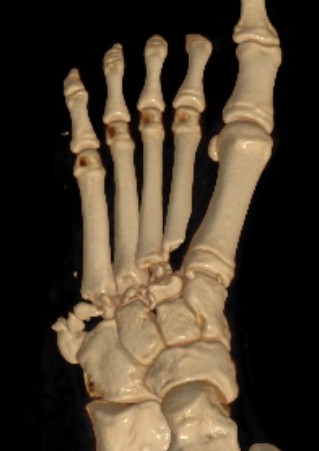

Anatomy

Bony Stability

| Alignment | Alignment | Roman arch | Keystone / Mortise |

|---|---|---|---|

|

1st metatarsal - medial cuneiform 2nd metatarsal - middle cuneiform 3rd metatarsal - lateral cuneiform

AP foot view |

4th and 5th metatarsals articulate with cuboid

Oblique foot view |

Bases of metatarsal wider dorsally than plantar Form half of Roman arch |

2nd metatarsal is keystone of transverse metatarsal arch - middle cuneiform is recessed proximally - mortise provided for base of second metatarsal |